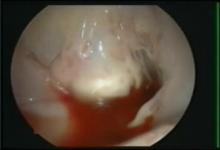

Thoracoscopic Mitral Valve Repair in Dilated Cardiomyopathy: A Case of Chordal Tethering [1]

By Saqib Masroor, MD, MIIS and John Alexander, MD